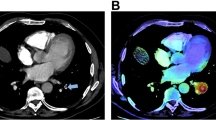

Per study, 16 studies had a reported iPE while 59 studies had an unreported iPE (total iPE prevalence 4.0%). Unreported iPE had a significantly lower number of involved vessels compared to reported iPE, with a median of 2 (IQR 1–4) versus 5 (IQR 3–9.75), p < 0.001 (Fig. 2a). Of the unreported iPE, 32/59 (54.2%) were proximal to the subsegmental arteries. In subsegmental and segmental iPE, the embolic burden varied between 1 and 7 involved vessels, and in lobar or more proximal iPE, between 4 and 15 vessels were involved (Fig. 2b). No significant differences were noted in age, cancer type, or enhancement of the main pulmonary artery between cases with unreported compared to reported iPE (281 vs 267 HU, p = 0.56).

The AI algorithm correctly identified 68 of 75 iPE with three false positives (sensitivity 90.7%, specificity 99.8%, PPV 95.6%, NPV 99.6%). False negatives occurred in cases with 1–3 involved vessels, none of which was originally reported. False positives were deemed to be caused by flow artifacts (n = 2) or perivascular infiltrates (n = 1). The AI compatibility analysis correctly identified 1888/1892 studies, whereas four studies were erroneously classified as NECT.

The most likely reason for the underreporting of iPE is search error rather than interpretation error (Figs. 3 and 4). As iPE most often have a very typical appearance, it is unlikely that the reporting radiologist detected an iPE and then deemed it to be a false positive finding. Since pulmonary artery opacification was high and thin slices were always available, underreporting is likely related to an unsystematic review of the pulmonary arteries, and underutilization of the thin slices. Tresoldi et al showed that there was a significant improvement in sensitivity (from 46–50% to 82–92%) when CT slice thickness was decreased from 5 to 1.25 mm [14]; in the present study, the thin axial slices, together with thicker reconstructed slices, were always sent to the PACS. These results are similar to the study by Bach et al who showed a 3.9% prevalence of iPE in cancer patients, of which almost 60% were unreported [8].

The AI algorithm had a very high sensitivity and specificity with only three false positives and seven false negatives (Fig. 5). In our study, the significant underreporting of iPE in combination with the accuracy of the AI algorithm shows that there is potential for AI to increase the detection rate of iPE. In addition, the CT studies could be analyzed quickly by AI while the patients are still at the radiology department. Studies with suspicious findings could then be triaged to a radiologist to reduce report turnaround time, and potentially reduce time to treatment. The high accuracy of the AI algorithm, and the low number of false positives especially, is a prerequisite to be useful in the clinical workflow as each AI finding needs to be evaluated swiftly. However, several aspects need to be considered if such an AI algorithm is implemented in clinical practice: as there will be radiologists with varying experience in PE diagnosis using the AI algorithm, there is a potential risk of overdiagnosis due to false positive findings; in addition, there is a risk of unnecessary additional tests to confirm a smaller iPE, for example, with CTPA. A clearly defined workflow needs to be in place to reduce these risks.